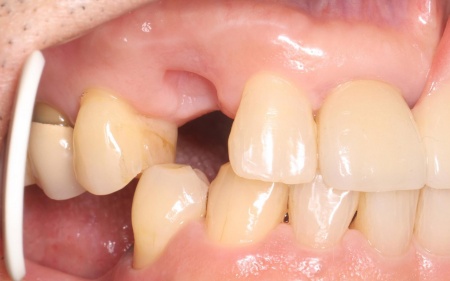

70代男性 歯根が割れた右上の前歯を抜歯後に部分入れ歯で治療した症例

定期検診で通院中の患者様に「噛むと右上の犬歯に痛みがある」とご相談いただきました。

拝見したところ、右上の犬歯には被せ物が装着されていました。

そこで、原因を詳しく調べるため被せ物を慎重に取り外し歯の内部を確認したところ、歯根が縦方向に割れる「歯根の垂直破折」が認められました。

この状態になると、隙間から細菌が入り込んで周囲の骨や歯ぐきに感染が広がったり、接着や修復による温存が困難になったりします。

また、このまま放置すると痛みや腫れが悪化し周囲の組織にも影響が及ぶ可能性があるため、抜歯が必要ですが、歯を抜いたままにすると隣の歯が動いて噛み合わせや歯並びに影響が出るおそれもあります。

以上のことから、抜歯したあとに歯を補う治療が必要と診断しました。

まず、感染の拡大を防ぐために右上犬歯の抜歯を行い、歯ぐきや骨が安定するまで一定期間経過を観察します。